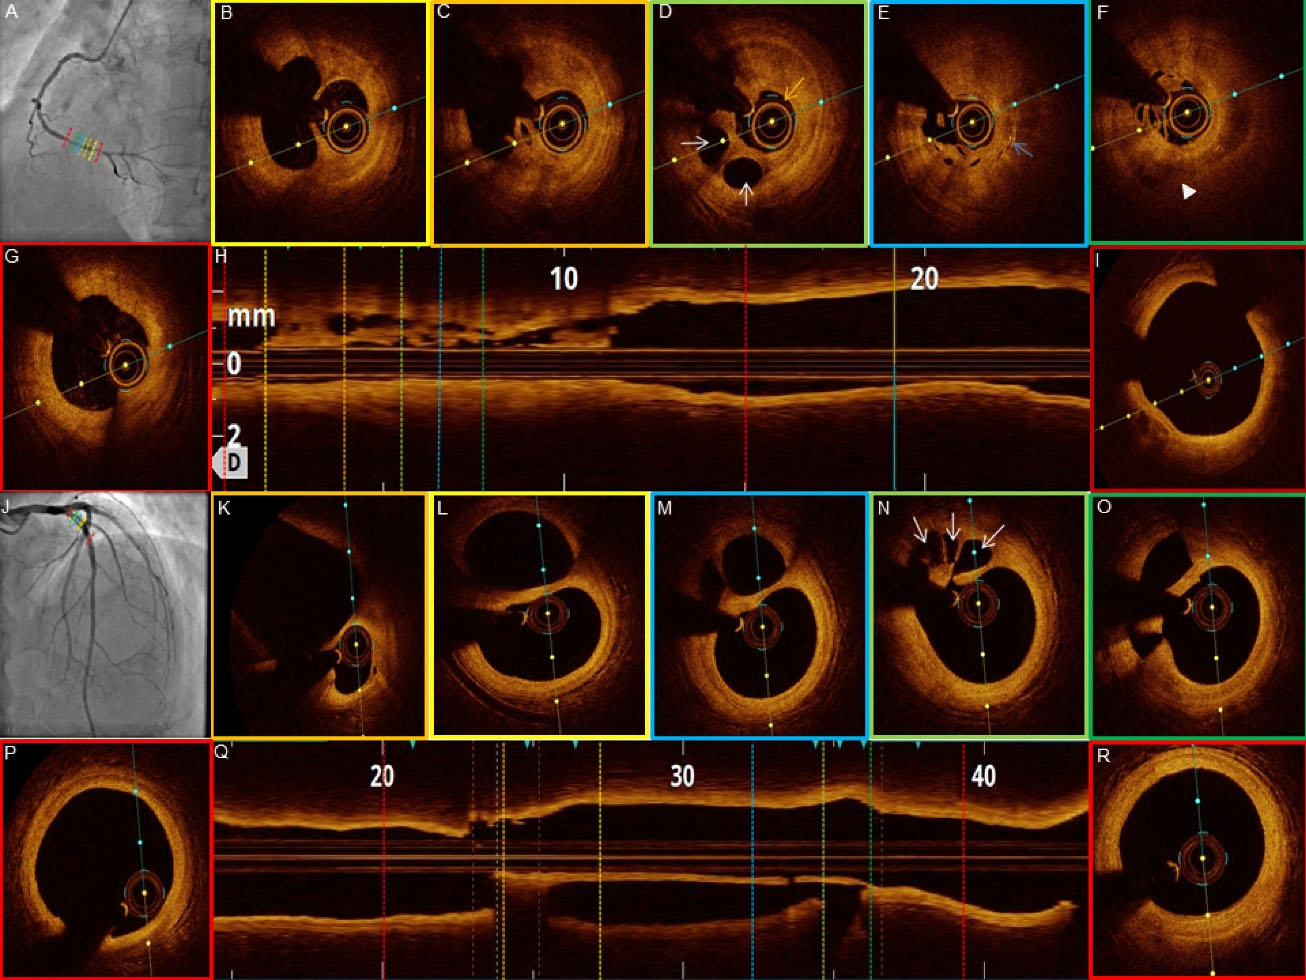

jcvtr-14-220-g005

Figure 5. OCT images of patient #7-8 (LCX) with near occlusion and veiled appearance respectively on angiogram (A and J). (E) Small cavities (white arrows) and catheter fiber (yellow arrow). (M) Lipid rich plaque (white arrowhead). (N) Plaque rupture with cavity (white asterisk), thin cap fibroatheroma 50µ (white arrow). (O) Medial dissection (blue arrows).